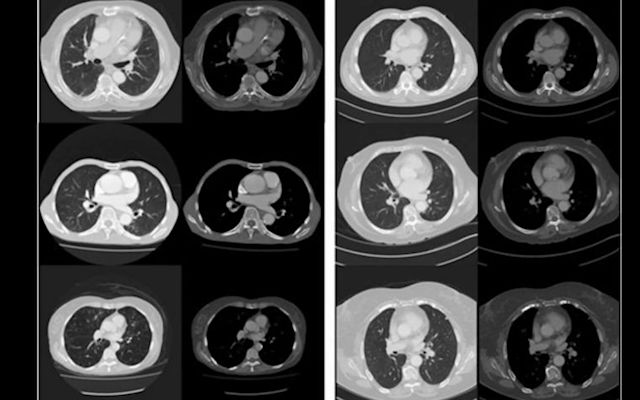

Se han presentado experimentos de prueba para demostrar cómo por la adquisición sistemática de imágenes a través de la TC de corte transversal se puede utilizar para predecir la longevidad del paciente como una guía para la salud individual y el estado general de la enfermedad mediante técnicas de análisis de imagen por ordenador. A pesar de las limitaciones de un conjunto de datos modesto y el uso de métodos de aprendizaje de la máquina, nuestros resultados son comparables a los métodos clínicos manuales previos para la predicción de la longevidad.

Este trabajo demuestra que las técnicas radiográficas pueden utilizarse para extraer biomarcadores relevantes para cada uno de los resultados más ampliamente utilizados en la investigación epidemiológica y clínica, sobre la mortalidad; y que el aprendizaje profundo con las redes neuronales convolucionales (redes neuronales artificiales) puede aplicarse de manera útil a la investigación radiológica. El análisis de imágenes computarizadas aplicado a imágenes médicas recopiladas rutinariamente ofrece un potencial sustancial para mejorar las iniciativas de medicina de precisión.

Investigadores de la Escuela de Salud Pública de la Universidad y la Escuela de Ciencias de la Computación, junto con colaboradores australianos e internacionales, utilizaron la inteligencia artificial para analizar la imagen médica de 48 pechos de pacientes. Este análisis computarizado fue capaz de predecir qué pacientes morirían dentro de cinco años, con el 69% de precisión, comparable a las predicciones «manuales» por los clínicos.

Presentamos un estudio preliminar de «prueba de principio» para evaluar la utilidad de la imagen médica para el fenotipado de la salud. Investigamos el análisis de la TC torácica de forma rutinaria en pacientes adultos (edad> 60) para predecir la longevidad. Elegimos la longevidad como nuestro resultado primario, ya que la mortalidad representa un resultado fácilmente obtenido y bien definido (en este caso, la tasa de mortalidad a los 5 años) y se correlaciona fuertemente con la presencia subyacente de enfermedad crónica. La fuerte relación entre la edad, la morbilidad y la mortalidad motiva la selección de la mortalidad a corto plazo como biomarcador sustituto para el estado general de salud. Las tomografías computarizadas son también la modalidad de imagen transversal menos variable a la estandarización de valores de píxeles y la relación definida entre los valores de píxeles y la densidad física del tejido. Finalmente, el tórax contiene tejidos directamente implicados en gran parte de la morbilidad y mortalidad en adultos mayores (es decir, en los pulmones, corazón, grandes vasos y otros órganos). Muchos de los métodos existentes de biomarcadores de imágenes cuantitativas relacionadas con la enfermedad crónica y la mortalidad utilizan CT imágenes de tórax.

Investigamos tanto el análisis de imagen tradicional con características definidas por humanos y técnicas de aprendizaje profundo («redes neuronales convolucionales») para esta tarea, ya que estas técnicas tienen diferentes fortalezas y debilidades. En particular, los métodos tradicionales de análisis de imágenes han sido previamente validados como un método para describir cambios sutiles en los tejidos, y el aprendizaje profundo ofrece el aprendizaje automático y sin hipótesis de características de imágenes complejas y de alto nivel.